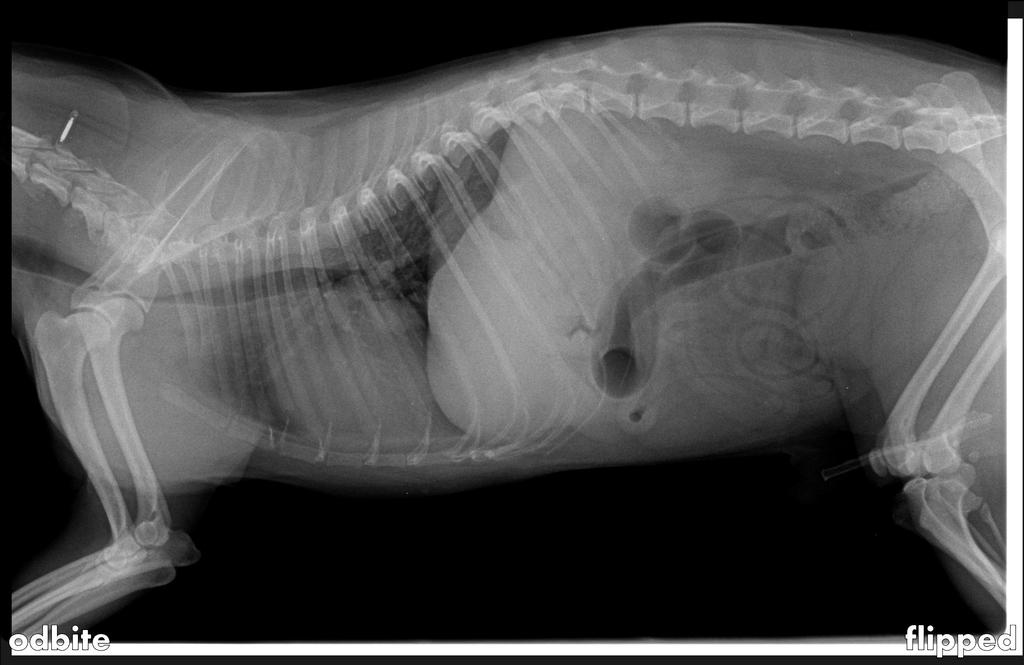

2. Witam, chodzi o pieska Tomi yorkshire terrier. Tomi bendzie mial w maju 13 lat, rok temu 2011 w zime pokazaly sie pierwsze objawy. Tomi zaczal piszczec mial bole i problem z tylniymi lapkami tzn. z krzyzem. Dostal zaszczyki (Rapidexon) ktore mu pomogly znowu sie poruszac niemial buli i bylo oki rok czasu (Zostalo zdrobione zdjecie rentgenowskie, w zalaczniku sie znajduje) . Dzisiaj ma Tomi znowu problemy tzn. juz tydzien czasu, dostaje znowu zaszczyki , tabletki na bol i kropelki do rozluznienie miesni. Czy zna moze ktos specjalisty w Polsce (Krakow, Wroclaw, Szczecin, obojetnie) jak chodzi o dobre porady. Mieszkam za granica tutaj lekarz mowil mi o operacji. Na zdjeciu widac w srodku krzyza nacis. Dowiedzialam sie ze to zwapnienie trzech kregow. Ciesze sie juz teraz na odpowiedzi i czekam pilnie!!!! DZIEKUJE!